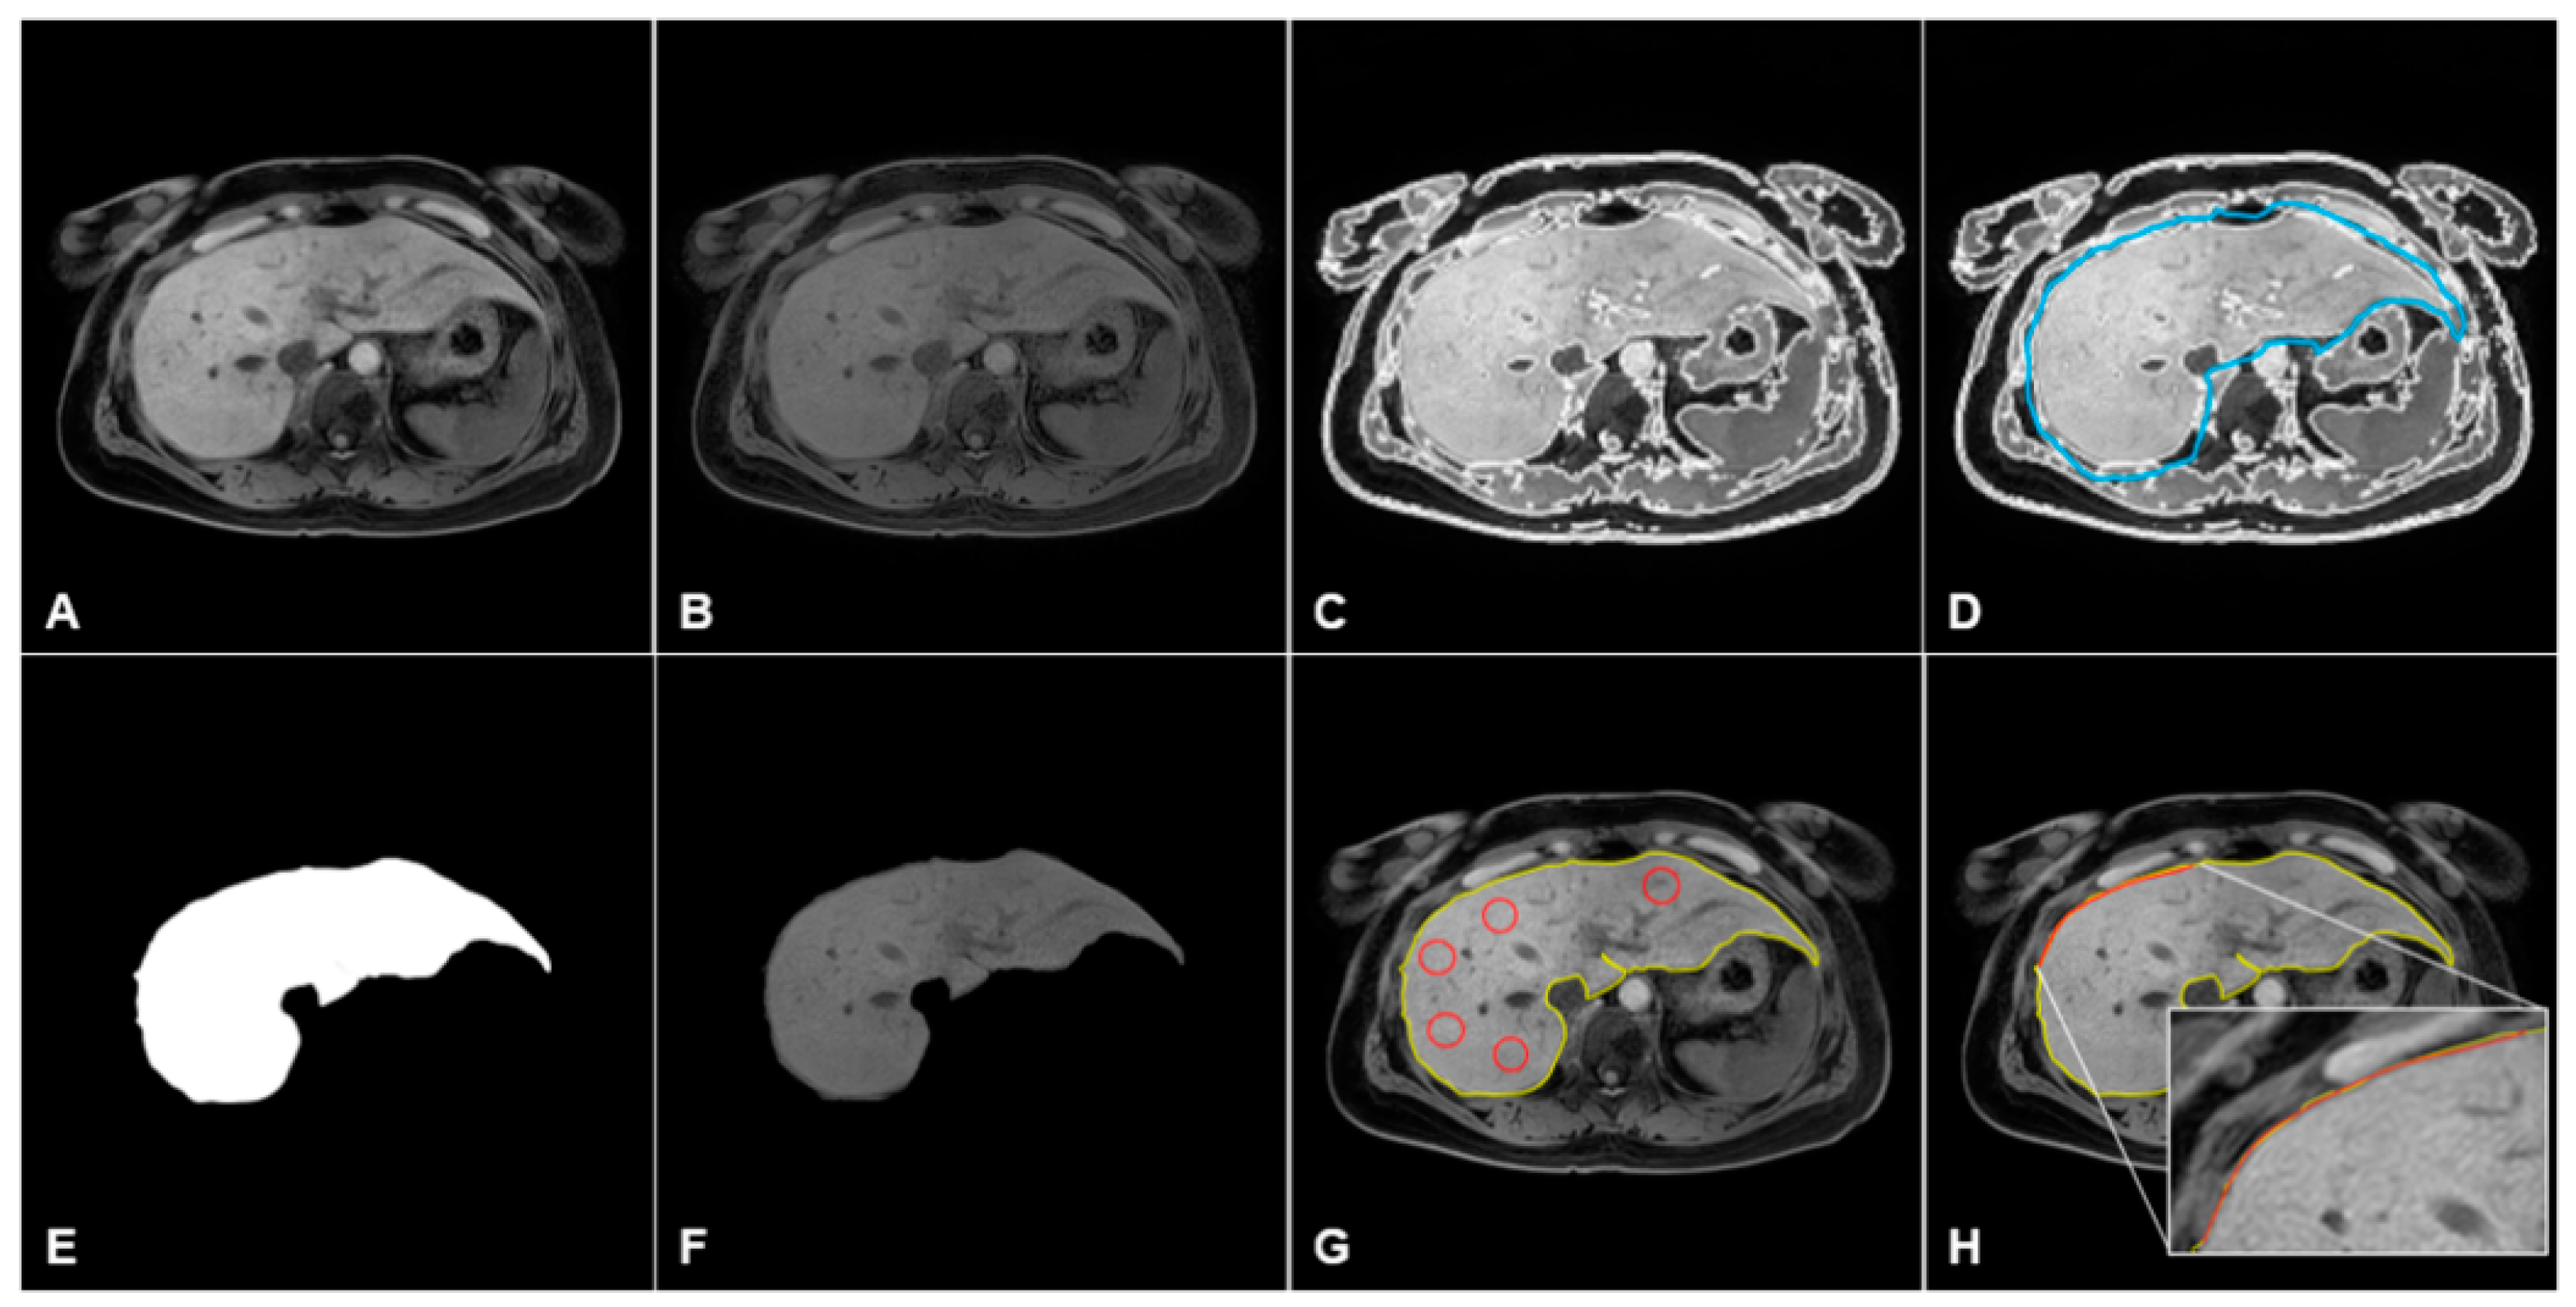

2.4. Software for Quantification of Liver Heterogeneity and Nodularity

2.5. Data Processing and Quantification of MRI in CLD